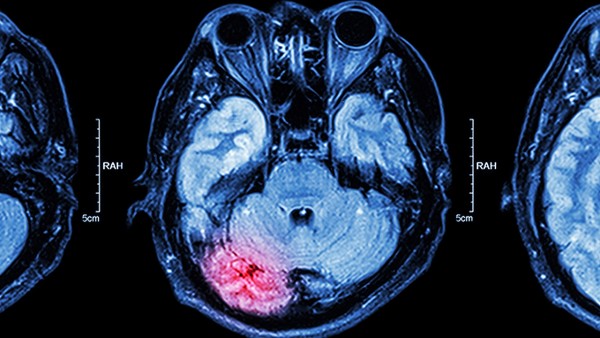

脑供血不足是指患者脑部某部位出现供血不足,导致脑功能障碍,该病主要与脑动脉硬化有关。不及时治疗,脑供血不足的情况持续发展可能会引起脑梗塞、痴呆症的发生,不仅如此,脑供血不足症状较轻时,对身体有一定程度的损伤。